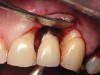

Figure 5  Excess cement noted below the crown margin resulting in peri-implant inflammation as shown in Figure 3. After facial and palatal flap elevation for direct visualization, excess cement was removed with curettes. Care was taken to avoid scratching the abutment surface. The site was irrigated with a 0.12% chlorhexadine-based oral rinse; flaps were replaced and closed with resorbable gut suture.

Figure 5